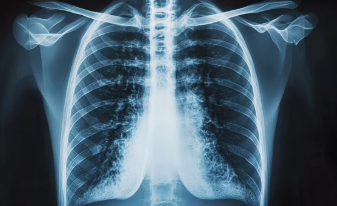

폐기흉(기흉, Pneumothorax)은 폐에 공기 주머니(기낭)가 터지거나 손상되면서 공기가 흉강(가슴막)으로 새어나와 폐가 수축하는 질환이다.

2. 폐기흉이 발생하는 주요 원인

② 이차성 폐기흉 – 기존 폐 질환이 있는 경우

✔ 만성 폐질환(만성 폐쇄성 폐질환, 폐기종, 결핵, 폐렴 등)으로 인해 발생

✔ 기저 질환이 있는 경우 증상이 더 심할 수 있음